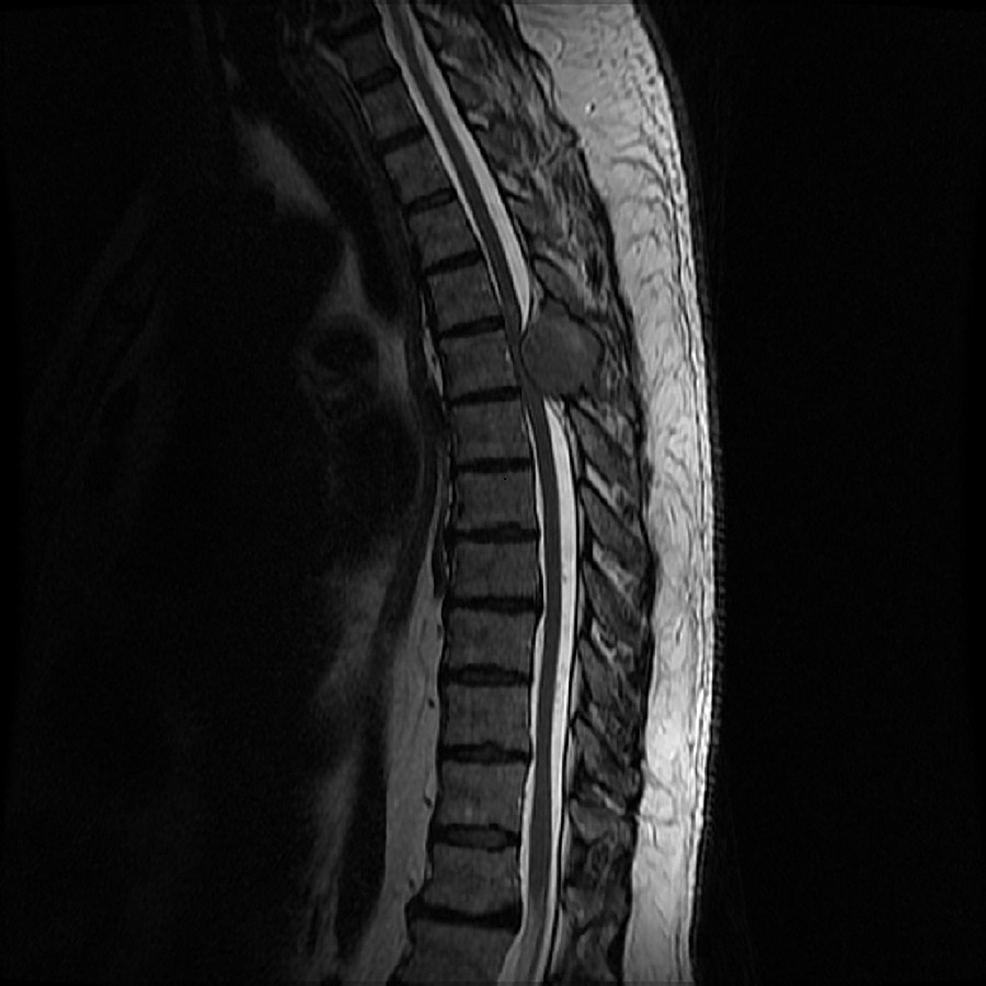

Spinal cord compression MRI wikidoc Spinal Cord Compression Recovery The immediate treatment for spinal cord injury is directed at reducing the permanent impact of the injury. The early stages of recovery involve hospital. Spinal cord injury recovery heavily relies on retraining your muscles, spinal cord, peripheral nerves, and brain to work in sync again. However, sometimes people experience partial or substantial recovery after a spinal cord injury. Advances in. Spinal Cord Compression Recovery.